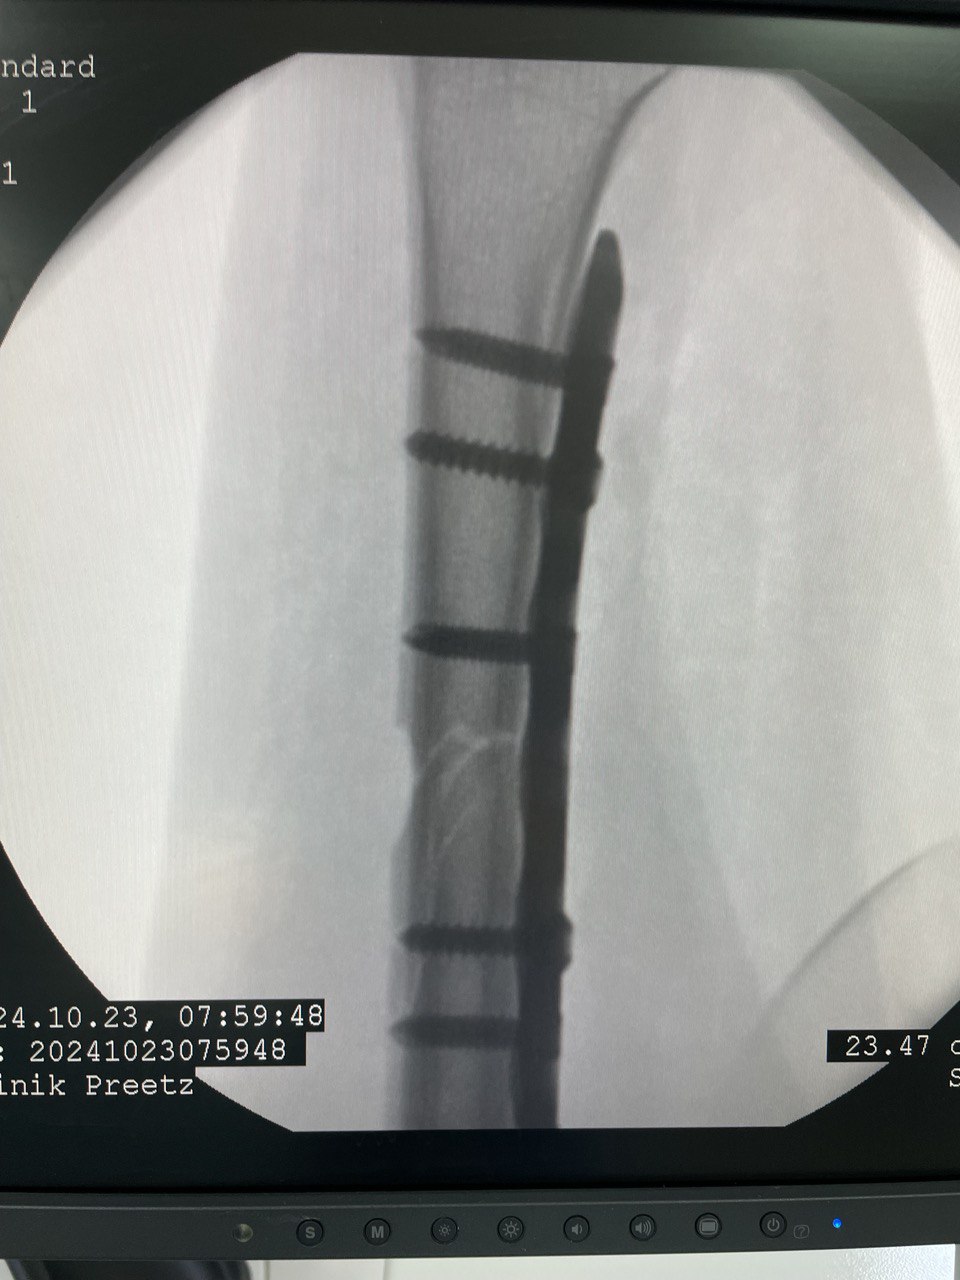

Клинический случай: внутрисуставной перелом дистального метаэпифиза лучевой кости — операция (остеосинтез пластиной)

Этап остеосинтеза: доступ, фиксация и контроль положения пластины.